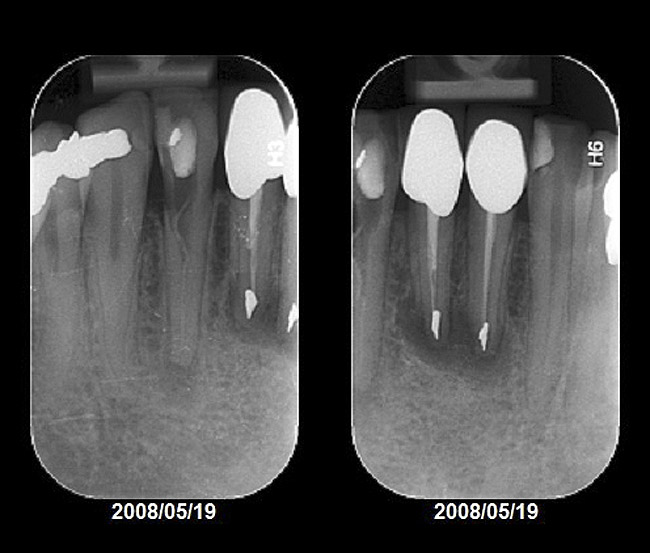

Figure 2  Initial periapical radiographs showing failed endodontic treatment of Nos. 24 and 25, and root resorption, No. 26.

Figure 2

Radiographic evidence of external root resorption on tooth No. 26 and periapical radiolucencies with a history of prior endodontic treatment, including apicoectomies, were present on the mandibular central incisors (Figure 2).